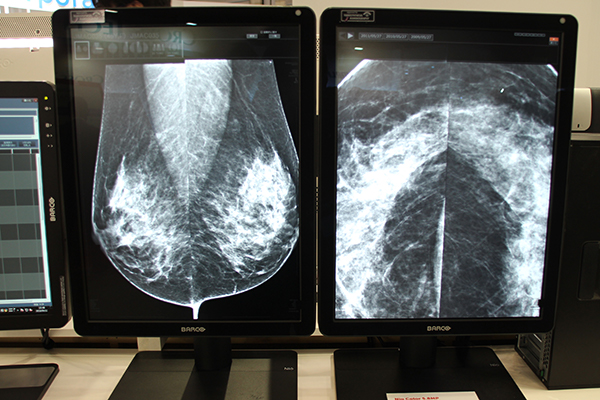

また,マンモグラフィ用画像表示ディスプレイ「Nio Color 5.8MP」も展示した。Nio Color 5.8MPは,5.8メガピクセルと一般的なマンモグラフィ用画像表示ディスプレイで採用されている5メガピクセルよりも大きな解像度表示をサポートしている。また,カラー表示に対応しているため,マンモグラフィはもちろん,超音波などのカラー画像も1画面で同時に表示できる。Coronis Unitiに搭載されているSteady ColorやSpotViewなどにも対応し,読影効率の向上に貢献する。

両製品は,照明を調整して読影室と同様の環境を再現したダークルームに設置され,実際の読影環境でディスプレイのパフォーマンスを体験できるようにしていた。

デジタルマンモグラフィ画像表示用カラーディスプレイNio Color 5.8MP